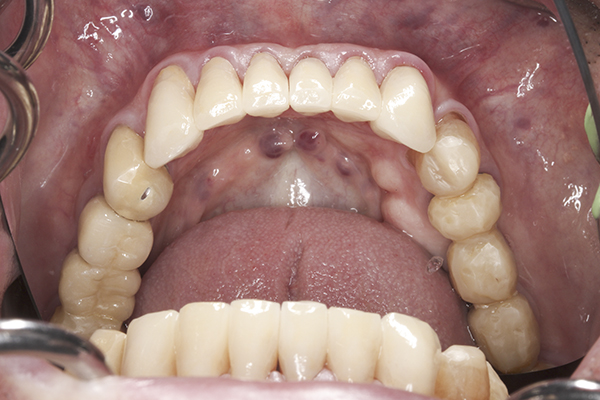

(1.) Lateral view of cross-section through the TMJ: [1] Posterior slope of the eminentia; [2] condyle; [3] disc; [4] superior lateral pterygoid muscle; [5] inferior lateral pterygoid muscle; [6] synovial tissue; [7] retrodiscal

tissue; [8] posterior ligamentous attachment of disc to condyle.

Figure 1

Also, constant tension within the superior belly of the lateral pterygoid muscle (the portion of the lateral pterygoid with attachments to the articular disc) will result in continuous stretching of the ligaments that attach the disc to the posterior surface of the condyle. This constant stretching can eventually create an unstable condyle-disc assembly, resulting in a disc that can click or pop off of and onto the lateral pole of the condyle during function (Figure 1).18 Further damage can be created if the medial aspect of the disc slides forward and off of the condylar head. This severe situation can result in the head of the condyle pressing against the highly innervated and vascular retrodiscal tissue. This can be experienced as extreme pain in the joint whenever the patient attempts to close their mandible or bite into food. If left untreated, this could eventually lead to bone-on-bone contact between the head of the condyle and the eminence and potential degeneration of the condylar head.19